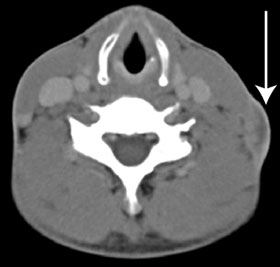

After the isolation of M. tuberculosis, the patient was initially treated in the community with standard first-line drugs. On receipt of the preliminary DST results, his urgent admission to hospital was arranged, with provision for isolation to prevent airborne disease transmission. A chest x-ray at this time showed fibrosis in the left upper zone, and a computed tomography (CT) scan showed an enlarged lymph node in the left anterior cervical chain (Box 3). The patient’s HIV serology results were negative, and an induced sputum sample set for TB was negative for acid-fast bacilli. Treatment was instituted with cycloserine 250 mg orally twice daily, para-aminosalicylic acid 4 g orally twice daily, linezolid 600 mg orally once daily, moxifloxacin 800 mg orally once daily, imipenem 1 g intravenously twice daily, clofazimine 200 mg orally once daily and isoniazid 600 mg orally once daily. The hospital pharmacy had difficulty in obtaining cycloserine, clofazimine and para-aminosalicylic acid. A 2-week supply of these agents was obtained from Auckland, New Zealand, but the remainder had to be imported from the United States.